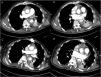

A 66-year-old man with a history of hypertension presented to the emergency department with a 7 -h history of severe chest pain. The patient was diagnosed with acute type A aortic dissection (ATAAD) and underwent urgent on-pump cardiac surgery. He started receiving low-dose anticoagulant therapy with 20 mg of enoxaparin twice per day on the 10th postoperative day. However, one week later, the patient suddenly developed hypoxemia but the hemodynamic state remained stable. Computed tomographic pulmonary angiography (CTPA) revealed normal pulmonary artery imaging and multiple filling defects in the left superior and inferior pulmonary veins (Fig. 1A and B, red arrows), indicating pulmonary vein thrombosis. The anticoagulant therapy was strengthened, with the dose of enoxaparin increasing to 60 mg twice daily. After a two-week strengthened anticoagulation, a follow-up CTPA indicated that these pulmonary vein thrombi were dissipated (Fig. 1C and D, red arrows). This is the first report of pulmonary vein thrombosis following ATAAD which is a rare but potentially lethal condition.